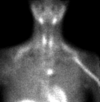

What pathology is seen in this image?

Phaeochromocytoma of the adrenal medulla